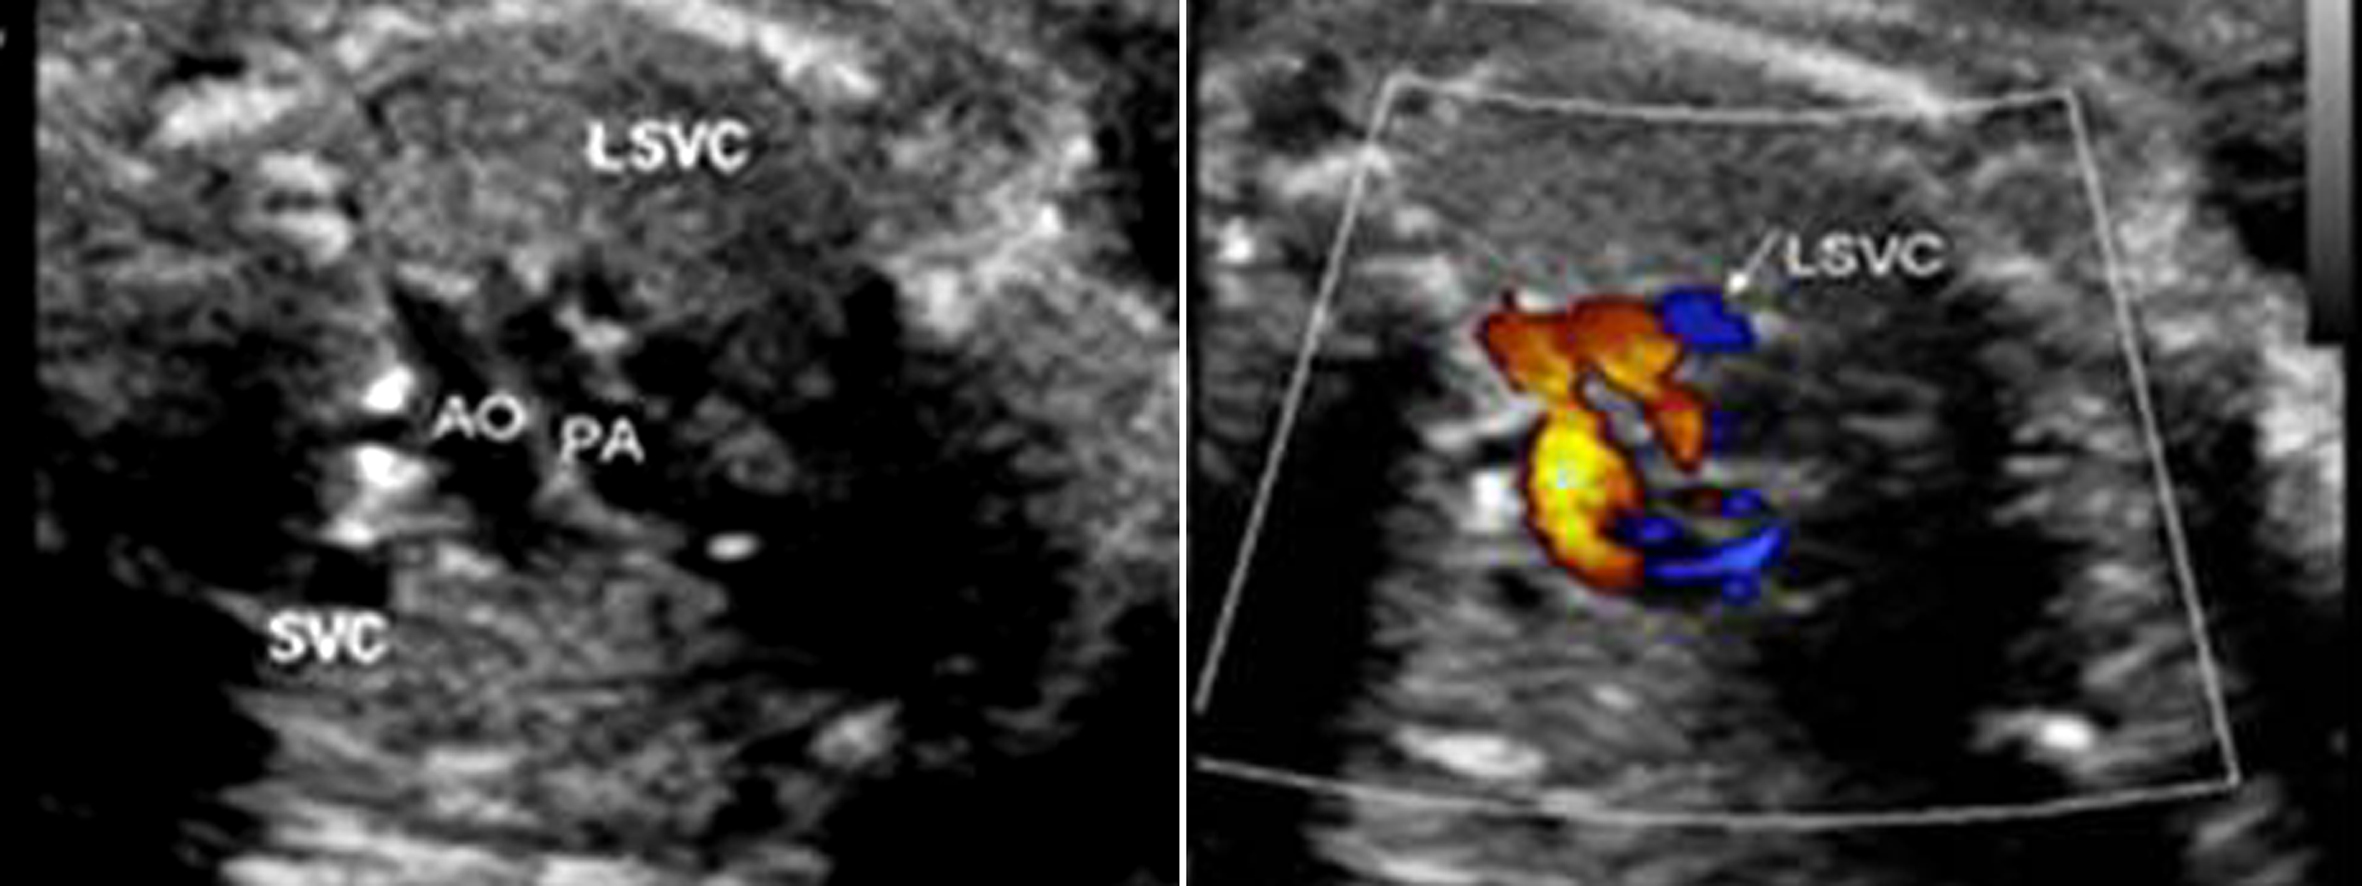

部分性AVSD超声图像特征为:房间隔的原发隔缺失,房室瓣与房室隔十字相交的正常结构消失,二、三尖瓣关闭时呈水平位,同时伴有二尖瓣和(或)三尖瓣反流,而室间隔完整,心室水平无分流(图3)。原发孔型ASD应与增大的冠状静脉窦相鉴别。前者心尖四腔切面观始终无法显示正常的十字交叉结构,后者声束在心尖四腔切面观靠后时显示等号状增大的冠状静脉窦,同时不能显示二尖瓣,而心尖四腔切面观时可见正常的十字交叉结构,并可见左侧房室沟处呈环状增大的冠状静脉窦(图4);另外,冠状静脉窦增宽常合并左侧上腔静脉永存,三血管气管切面在肺动脉左侧可见与右侧上腔静脉对称的血管即左侧上腔静脉(图5)。

图5 胎儿左侧上腔静脉永存三血管切面观